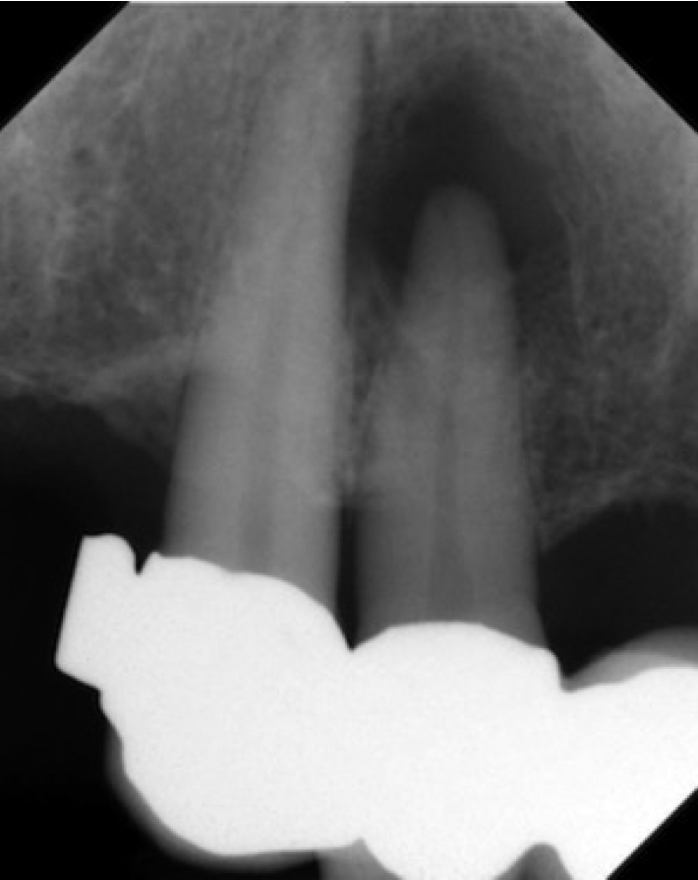

• Primärbehandlung Zahn 12

Parodontitis apicalis am Zahn 12 mit großer periapikaler Osteolyse als Nebenbefund eines Rö-Status vor PA-Therapie.

Echte Zysten sind eher selten. Meist handelt es sich auch bei so großen und relativ scharfbegrenzten Aufhellungen um Granulome. Granulome heilen im Gegensatz zu Zysten nach erfolgreicher endodontischer Behandlung meist knöchern aus.

Somit ist die Ersttherapie und in der Regel auch alleinige Therapie die orthograde Wurzelbehandlung.

Nur bei Fällen in denen die Osteolyse nicht rückläufig ist oder sich vergrößert, schließt sich eine Zystektomie mit apikaler Kürettage an.

Im vorliegenden Fall wurde der Zahn lege artis aufbereitet, desinfiziert und verfüllt. Die Röntgenkontrolle nach 6 Monaten lässt eine nahezu vollständige Ausheilung vermuten.

Die Brückenkonstruktion konnte somit auch erhalten werden.